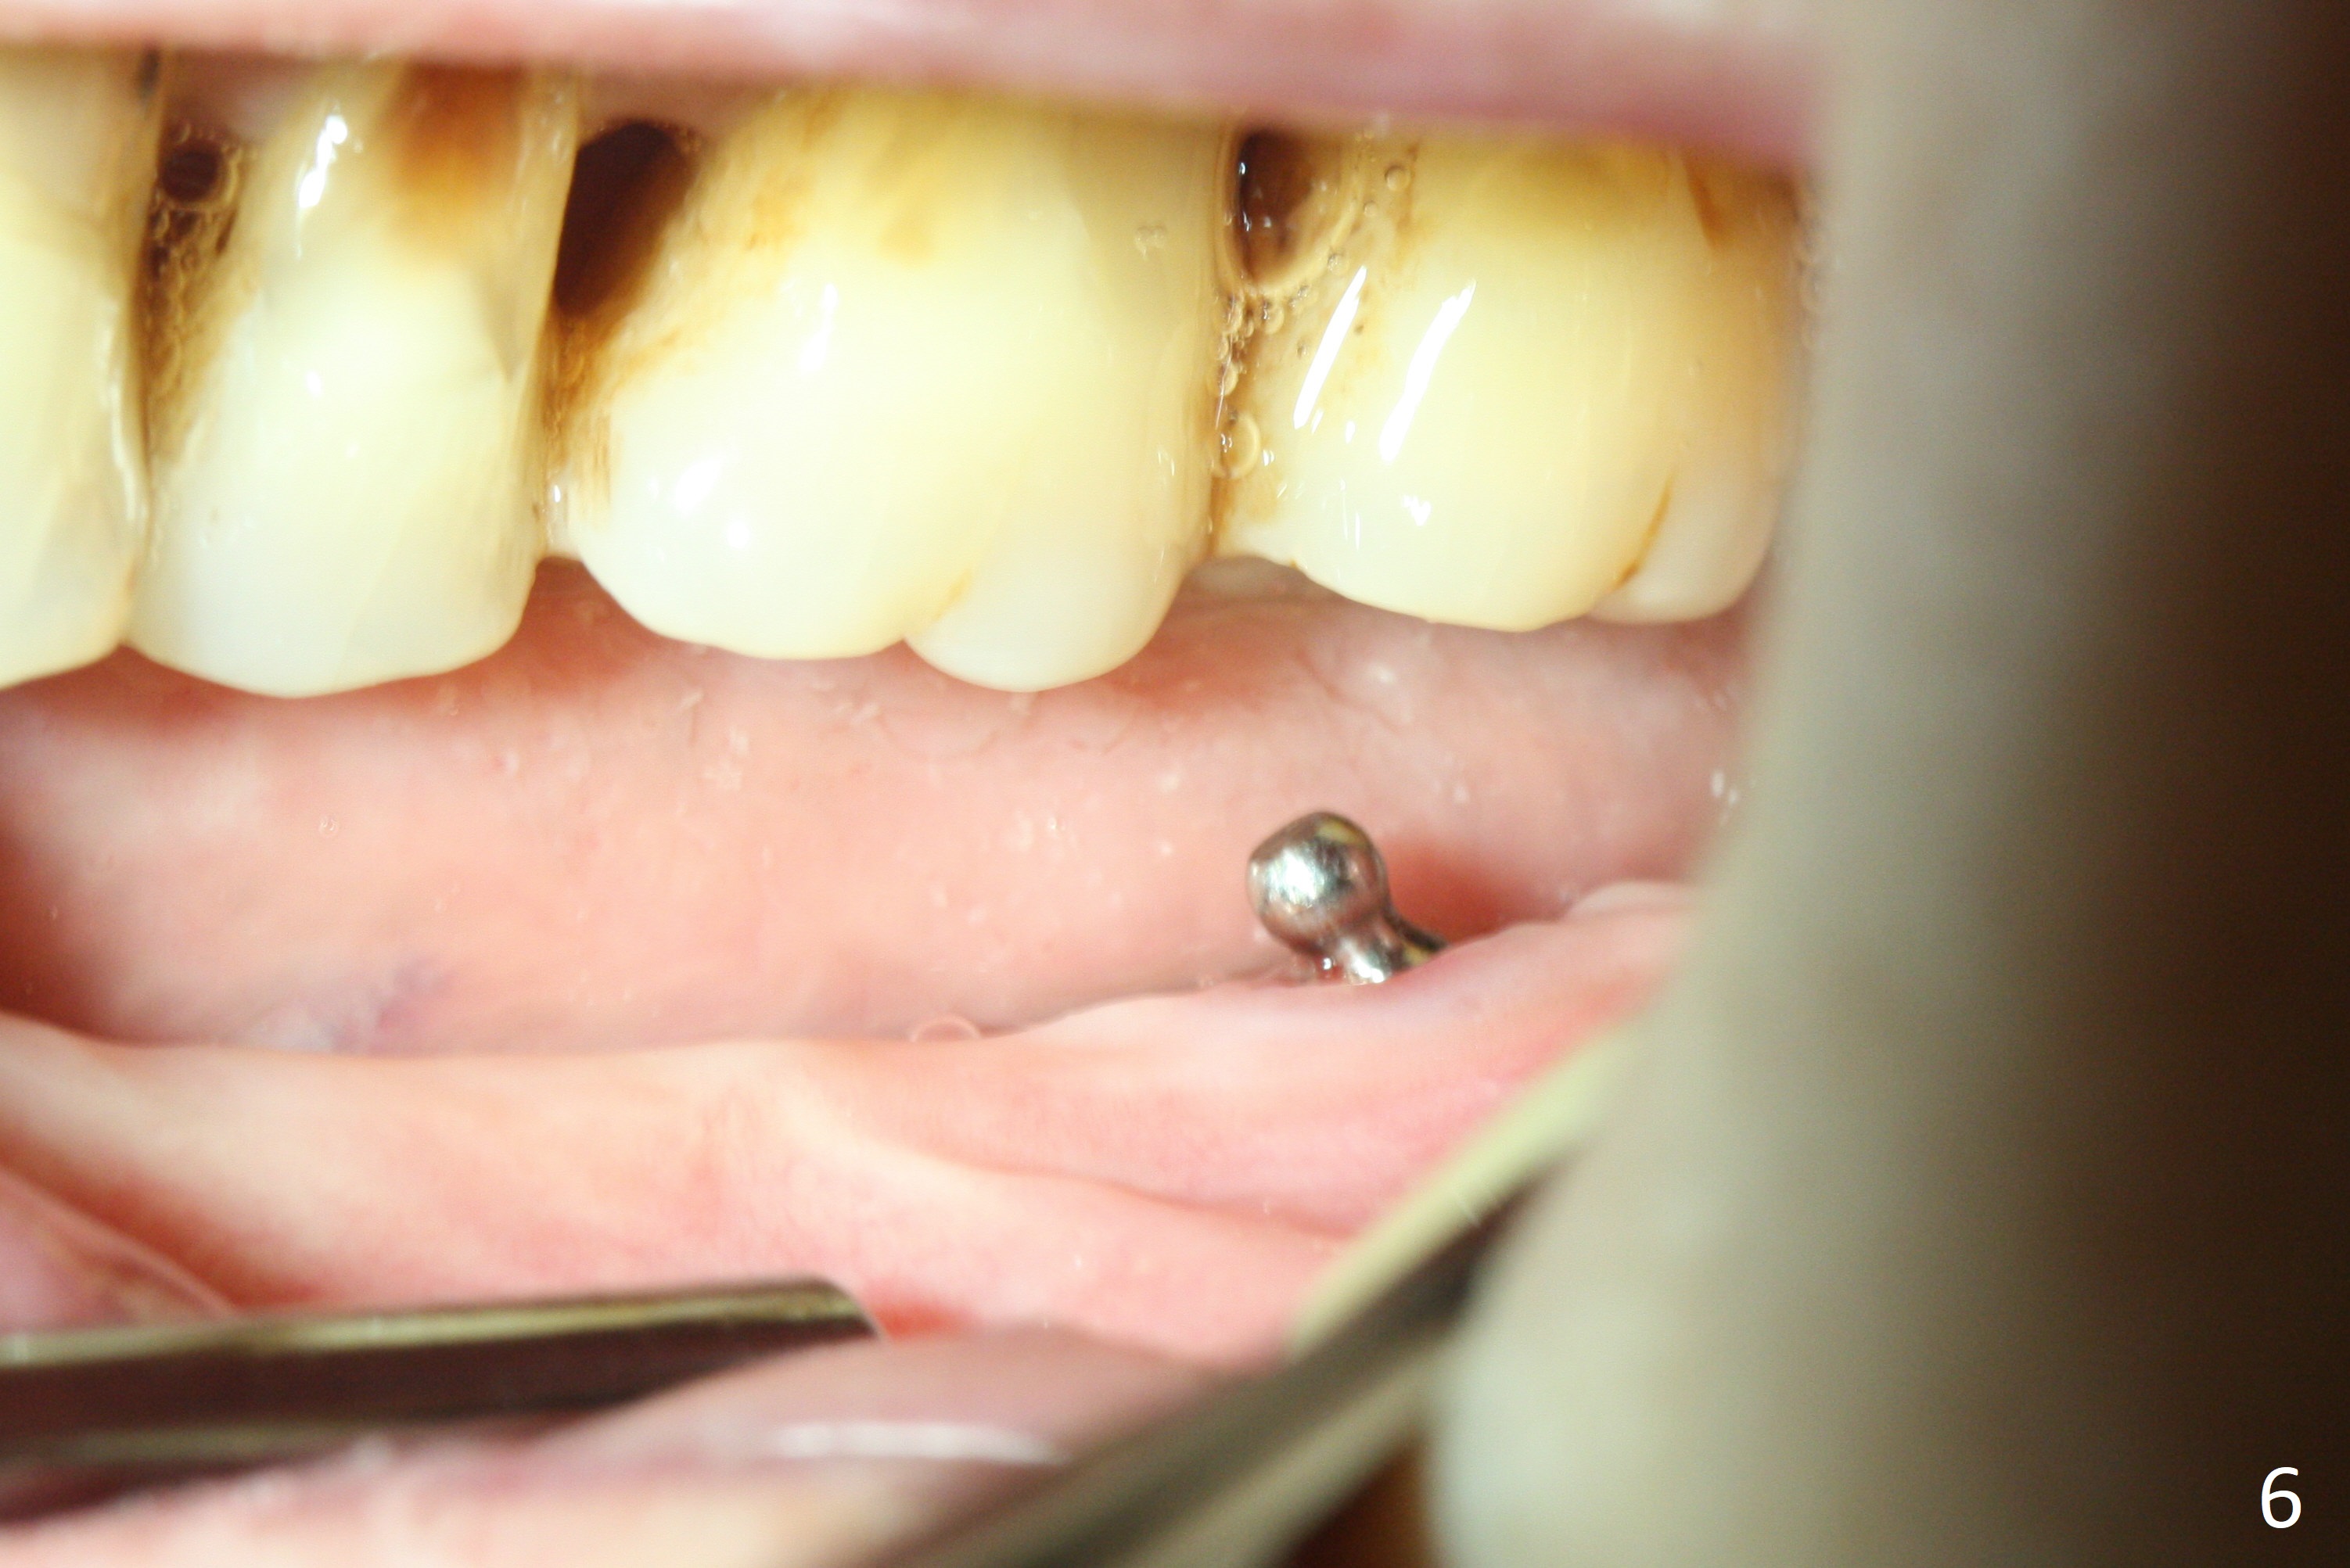

Preop photo confirms the lower left posterior pointed ridge (Fig.1). After ridge reduction and 2 mm drill for 8 mm, a parallel pin is inserted (Fig.2). A 3.8x8 mm SM implant is placed with >50 Ncm (Fig.3). The coronal threads (buccodistal) is covered with VeraGraft after placement of 4.1x5(3) mm healing abutment. The tooth #17 is not planned for extraction while the implant is osteointegrated. The tooth appears to be too loose and is extracted ~ 1.5 months postop. The implant seems to be osteointegrated 3 months postop (Fig.4). The healing abutment is changed to ball abutments with 4 mm (Fig.5) and 2 mm (Fig.6) cuffs. In fact the latter stays. What is the special device at the site of #18 (ring, Fig.7 <)?